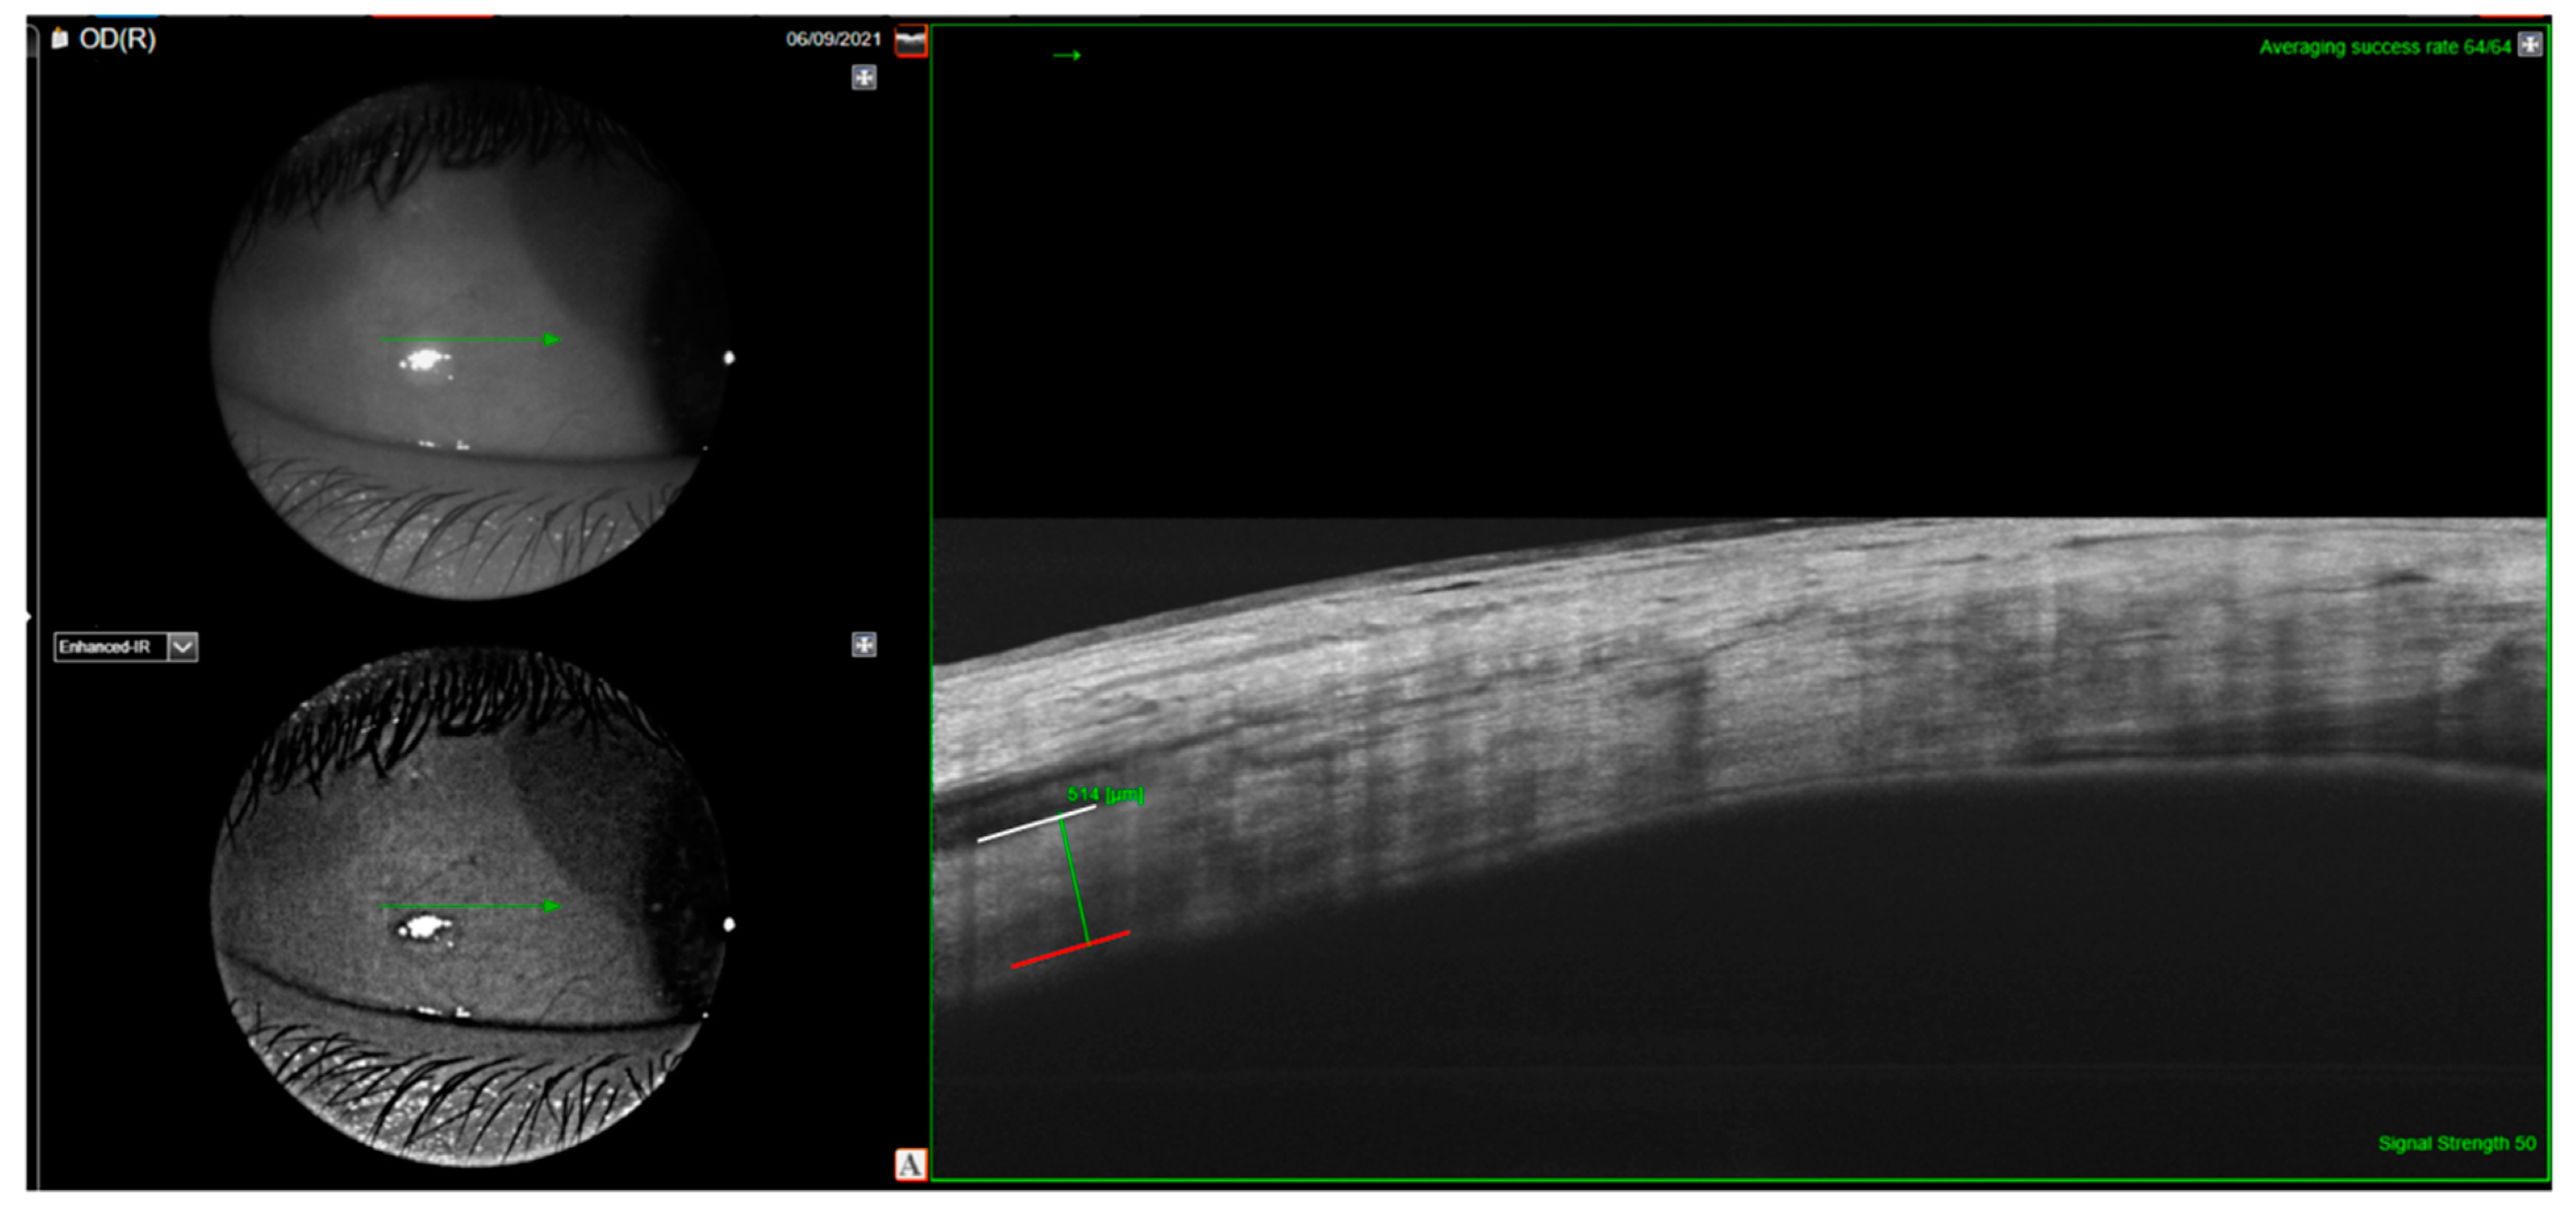

- Buckhurst, H.D.; Gilmartin, B.; Cubbidge, R.P.; Logan, N.S. Measurement of Scleral Thickness in Humans Using Anterior Segment Optical Coherent Tomography. PLoS ONE 2015, 10, e0132902. [Google Scholar] [CrossRef]

- Imanaga, N.; Terao, N.; Nakamine, S.; Tamashiro, T.; Wakugawa, S.; Sawaguchi, K.; Koizumi, H. Scleral Thickness in Central Serous Chorioretinopathy. Ophthalmol. Retin. 2020, 5, 285–291. [Google Scholar] [CrossRef]

- Lee, Y.J.; Lee, Y.J.; Lee, J.Y.; Lee, S. A pilot study of scleral thickness in central serous chorioretinopathy using anterior segment optical coherence tomography. Sci. Rep. 2021, 11, 5872. [Google Scholar] [CrossRef]

| Anterior scleral thickness (µm) | 403.5 ± 68.6 (278 to 619) | 362.5 ± 62.6 (218 to 493) | p = 0.028 |